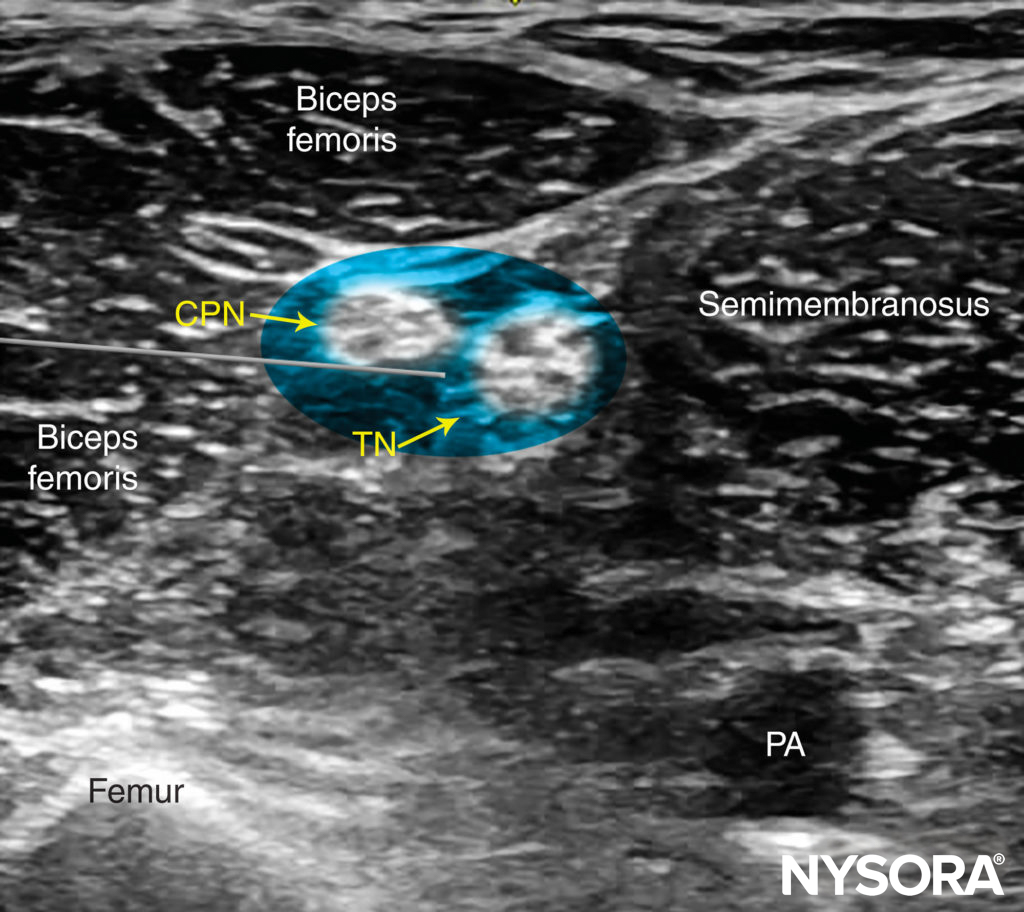

Beginning with the transducer in the transverse position at the popliteal crease, the popliteal artery is identified, aided with color Doppler US when necessary, at a depth of approximately 3–4 cm. The popliteal vein accompanies the artery at it is positioned just superficial (posterior) to it. On either side of the artery are the biceps femoris muscles (laterally) and the semimembranosus and semitendinosus muscles (medially). The tibial nerve is positioned superficial and lateral to the vein and is seen as a hyperechoic, oval or round structure with a honeycomb pattern (Figure 3). Asking the patient to dorsiflex and plantar flex the ankle makes the two sciatic nerve branches twist or move in relation to each other. Usually, tilting the transducer caudally is necessary to bring out the nerve from the neighboring adipose tissue.

FIGURE 3. Sonoanatomy of the sciatic nerve at the popliteal fossa. The two main divisions of the sciatic nerve, the tibial nerve (TN) and the common peroneal nerve (CPN), are seen immediately lateral and superficial to the popliteal vein (PV) and artery (PA). This image was taken at 5 cm above the popliteal fossa crease, where the TN and CPN have just started diverging.

• Ultrasound imaging should specifically focus on identifying the sciatic nerve sheath (Vloka’s sheath) containing both components of the sciatic nerve (tibial and common peroneal nerves). Successful injection will deposit local anesthetic within the Vloka’s sheath

The goal is to inject the local anesthetic within the common connective tissue (Vloka’s) sheath that envelops the TN and CPN. Alternatively, separate nerve blocks of TN and CPN can be performed.

It is recommended to perform the nerve block at the level where TN and CPN start diverging but are still in the common sciatic nerve (Vloka’s) sheath. For the lateral approach, a skin wheal is made on the lateral aspect of the thigh 2–3 cm above the lateral edge of the transducer, and the needle is inserted in plane in a horizontal orientation from the lateral aspect of the thigh and advanced toward the sciatic nerve (Figures 7 and 8).

For the posterior approach, the needle is inserted in plane from lateral to medial (Figure 9) or out of plane (Figure 10). If nerve stimulation is used (0.5 mA, 0.1 msec), the contact of the needle tip with either branch of the nerve usually is associated with a motor response of the calf or foot. Once the needle tip is placed within the common sciatic nerve sheath, 1–2 mL of local anesthetic is injected to confirm the proper injection site. Such injection should result in a distribution of local anesthetic within the sheath, and separation of the TN and CPN within Vloka’s sheath (Figure 11).

When local anesthetic injection does not appear to result in a spread inside the sciatic nerve sheath and around the sciatic nerve components, additional needle repositions and injections may be necessary. Correct injection is recognized when local anesthetic spreads proximally and distally to the site of the injection around both divisions of the nerve, which can be documented by observing the spread of the local anesthetic within Vloka’s sheath proximal to the site of injection. A single injection of local anesthetic typically suffices.